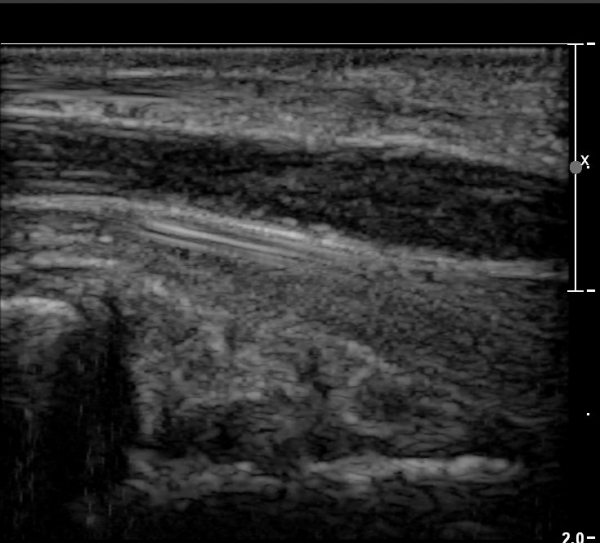

ÀÌ·± ¸ð½ÀÀº ¼Õ¸ñÀÇ ¿ù»ó°ñ ºÎÀ§(»çÁø 3, 4)¸¦ Áö³ª ¼ö±Ù°ü ±ÙÀ§ºÎ ±îÁö À̾îÁü(»çÁø 5).

ÇÏŰ½ºÆ½(°íÁÖÆÄ) ŽÃËÀÚ¸¦·Î °üÂûµÈ ¸ð½À¿¡¼­ Á¤Áß½Å°æ ºÎºÐ ½Å°æ´Ù¹ßÀÇ Àú¿¡ÄÚ

º¯È­°¡ ¶Ñ·ÈÇÔ(»çÁø 6, 7).